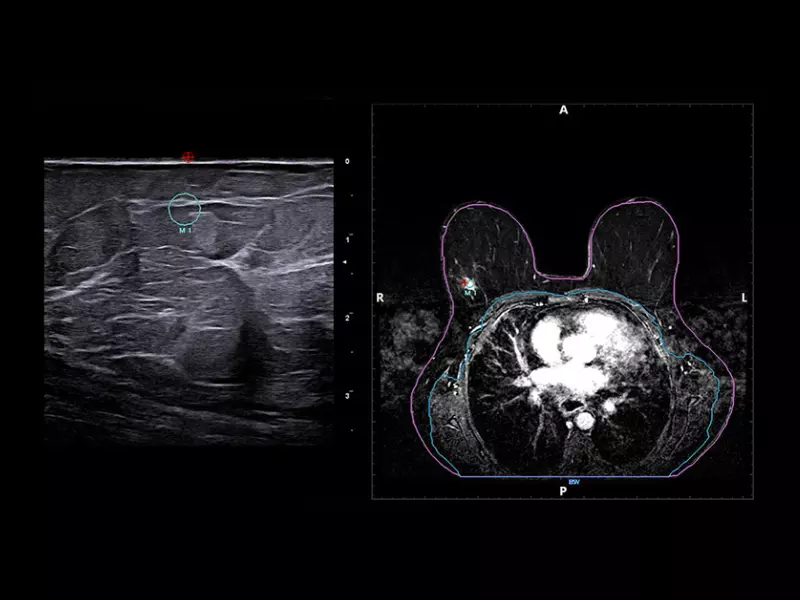

MyLab™X90 - BreastNav™ MRI Automatic segmentation of the breast MRI and real-time fusion based on an adaptive 3D mod

MyLab™X90 - BreastNav™ MRI Automatic segmentation of the breast MRI and real-time fusion based on an adaptive 3D mod